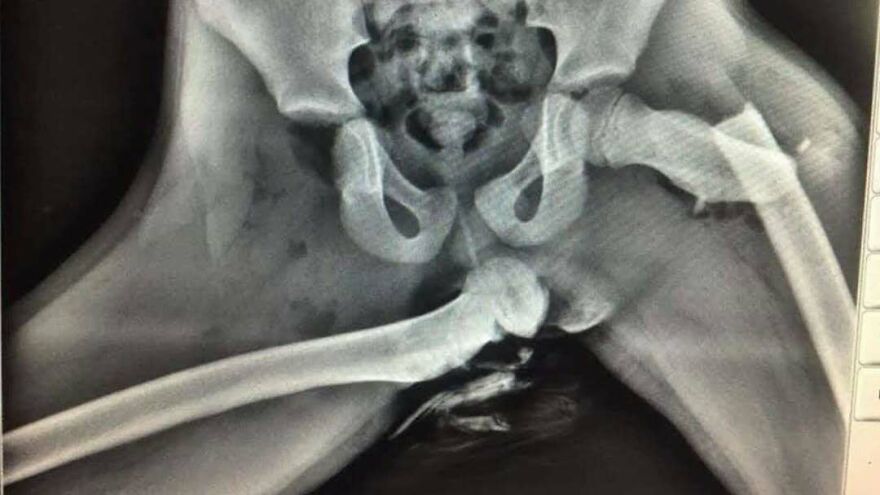

OtrosFEB 3, 202650 Medical Pics That Are Weirdly Mesmerizing And Slightly DisturbingLoKKie71CompartirWhy you should never put your feet on a car dashboard.A woman has sustained horrific injuries after resting her feet on the dashboard of a car. It left her with a crushed hip. Source: www.instagram.com71Compartir¿Qué opinas?Load More Comments